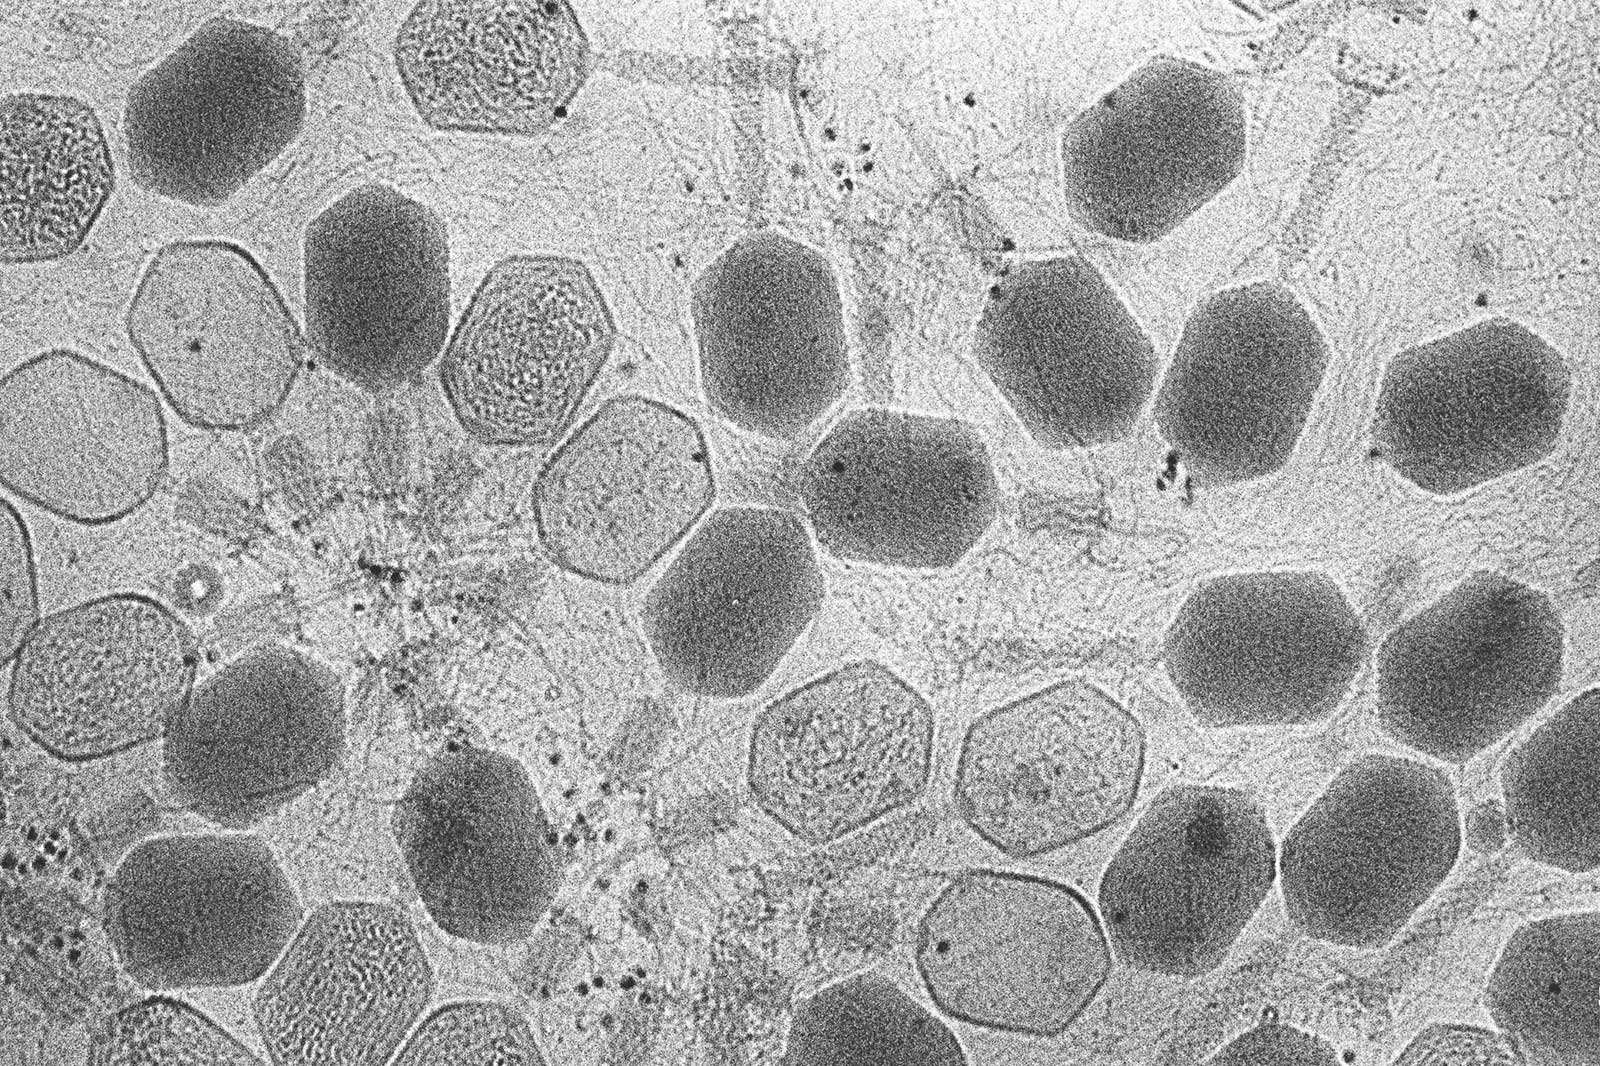

كشفت دراسة علمية حديثة جانباً غامضاً ومدهشاً من عالم الفيروسات، موضحةً أن لديها القدرة على مراقبة البيئة التي تتكاثر فيها.

وأثارت الدراسة، التي أجرتها جامعة ماريلاند بمقاطعة بالتيمور، جدلاً بشأن إمكانية استخدام المعلومات من قِبل الفيروسات، واصفةً ذلك بالقول إن الفيروسات قد تكون لها «عيون وآذان».

وأوضح الباحثون، حسبما أفاد موقع «الشرق الأوسط» نقلاً عن موقع «EurekAlert» العلمي المتخصص، أن الفيروسات تستخدم المعلومات من بيئتها لتقرر متى تجلس بإحكام داخل مضيفها ومتى تتكاثر وتنفجر، ما يؤدي إلى قتل الخلية المضيفة، وأن العمل على هذا الاقتراح له آثار في تطوير الأدوية المضادة للفيروسات.

وركز البحث الجديد على العاثيات (الفيروسات التي تصيب البكتيريا وغالباً ما يشار إليها ببساطة باسم العاثيات)، إذ لا يمكن أن تصيب العاثيات في الدراسة مضيفيها إلا عندما تكون للخلايا البكتيرية زوائد خاصة تسمى «الشعيرة والسوط»، والتي تساعد البكتيريا على الحركة والتزاوج، إذ تنتج البكتيريا بروتيناً يسمى CtrA يتحكم في وقت تكوين هذه الزوائد.